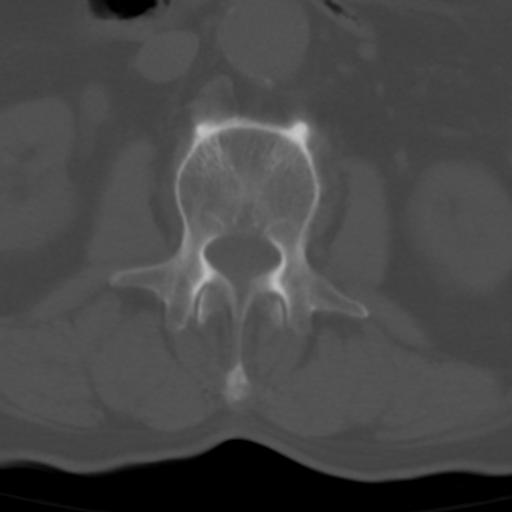

男性 82 主动脉夹层 请大家看看椎体是什么改变啊

腰椎退行性变,明显的骨赘形成,所指低密度灶为正常松质骨。